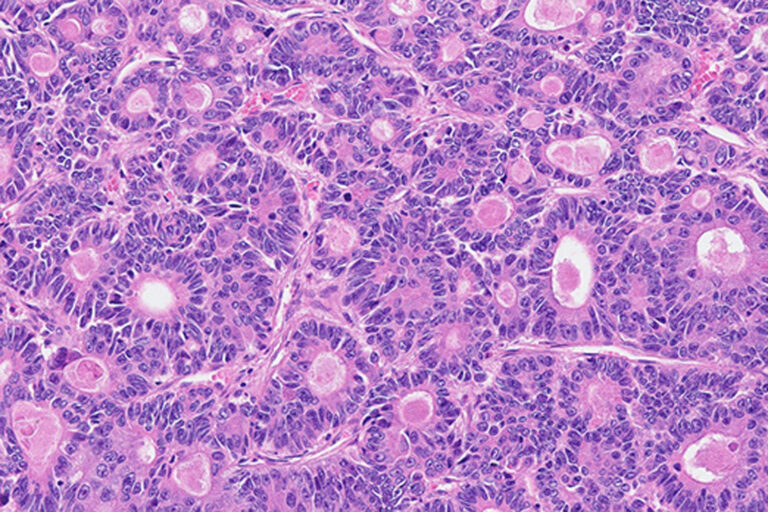

Darmkrebs unter 50